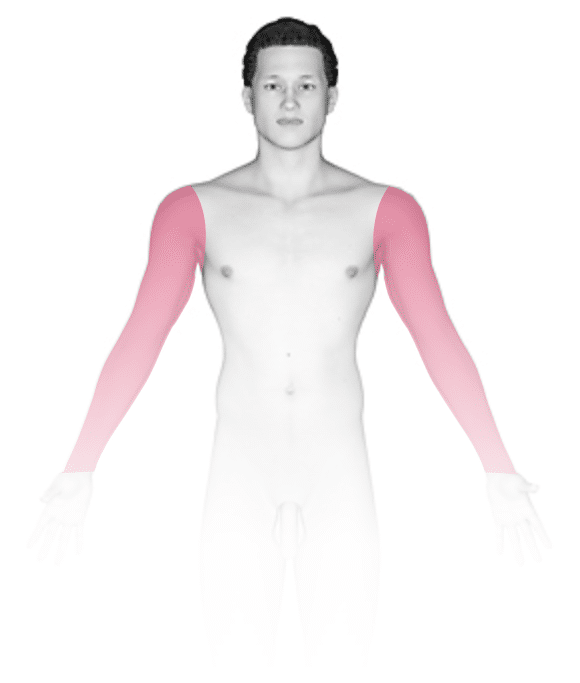

Cutaneous Anthrax

- Characteristic rash*

*The characteristic rash of anthrax looks like pink, itchy bumps that occur at the site where B. anthracis comes into contact with scratched or otherwise open skin. The pink bumps progress to blisters, which further progress to open sores with a black base (called an eschar). The early rash (the pink, itchy bumps) looks like many other rashes, so a history of exposure to the bacterium will be important to making the diagnosis. The eschar is more characteristic of anthrax infection, but if diagnosis and treatment are delayed until the eschar appears, the prognosis is poor.